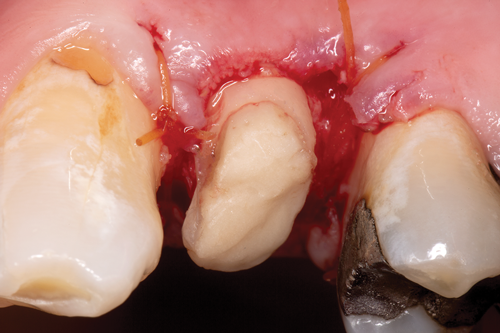

Restorative failure of an existing amalgam restoration on the maxillary left first premolar from recurrent caries is documented here (Figure 2). The periapical radiograph revealed an extensive carious lesion extending into the pulp chamber. After clinical and radiographic evaluation, a treatment plan was discussed with the patient that included endodontic therapy, crown lengthening, and reinforcing the root and supporting the tooth-restorative complex with a fiber-reinforced post and core system.

After completion of the endodontic treatment and crown lengthening to develop an ideal ferrule effect (Figure 3 through Figure 5) a diagnostic wax-up was fabricated to an ideal coronal preparation geometric shape, dimension, and height for the anticipated final composite core buildup (Figure 6). A clear polyvinyl siloxane (PVS) impression material was injected into a nonperforated tray, placed over the diagnostic wax-up, and then put into a pressure pot with cold water for 5 minutes. This procedure is aimed at reducing the potential for the formation of voids and bubbles in the impression material (Figure 7 and Figure 8). A small opening was made above the tooth to be restored using a tapered diamond bur (6847) (Figure 9). It is important to clean the internal surfaces with a microbrush to prevent silicone debris from integrating into the flowable material. Prior to the restorative procedure, a diagnostic wax-up was fabricated to the anticipated extracoronal contours for development of the final crown (Figure 10).

Fig 3. After endodontic treatment, crown lengthening was performed to develop an ideal ferrule effect.

Figure 3

Fig 4. An adequate collar effect of 2 mm of sound tooth structure would provide an anti-rotational feature for the stability of the crown.

Figure 4

Fig 5. Buccal view of optimal ferrule effect with a healthy biological framework.

Figure 5